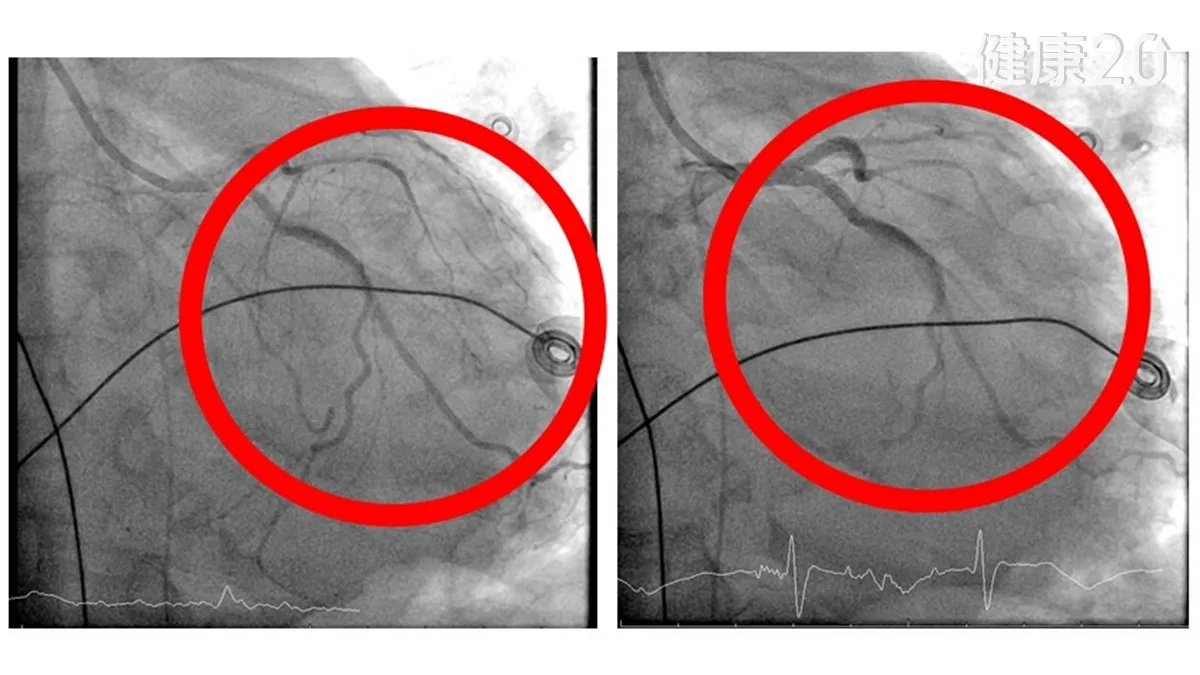

7小時心導管手術與生命拔河

在葉克膜支持下,心臟科團隊為患者進行長達7小時的心導管手術治療,處理多處嚴重冠狀動脈阻塞,並放置支架恢復血流。同時透過主動脈內氣球幫浦輔助心臟輸出,減輕心臟負擔。手術後患者血流動力逐漸穩定,心臟功能開始恢復,為後續治療爭取寶貴時間,也讓原本瀕危的生命出現轉機。

◎ 圖片來源/衛福部豐原醫院提供